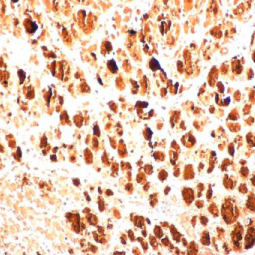

| GeneTex为EV71研究提供出色的抗体,请查看下面热门的EV71研究产品。 |